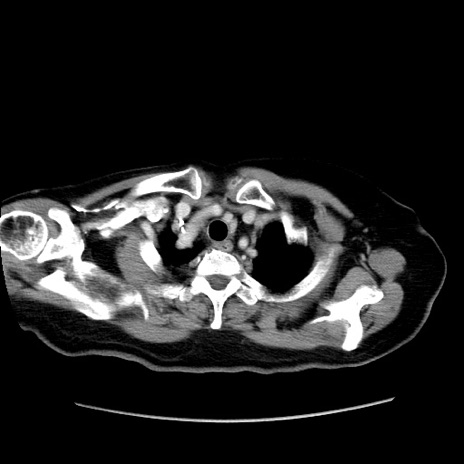

冠状断像

【症例】80歳代女性

【主訴】下腹部痛

【現病歴】約8時間前より下腹部痛の出現あり、救急外来受診。

【既往歴】両側付属器切除

【身体所見】意識清明、下腹部正中に手術痕あり、その部位に一致して圧痛と反跳痛あり。腸蠕動音は亢進。

【データ】WBC 9300、CRP 0.15